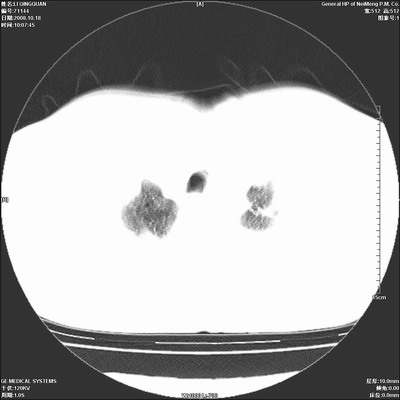

以下是引用duguo在2008-10-19 13:59:00的发言:[br]左肺上叶支气管狭窄,首先考虑中心型肺癌伴阻塞性肺炎\\肺不张.

以下是引用ybing在2008-10-19 12:58:00的发言:[br]左肺上叶阻塞性炎症-建议支气管镜进一步检查除外中央型肺癌

以下是引用随光逐影在2008-10-19 14:31:00的发言:[br]考虑左肺中央型肺癌并左肺上叶阻塞性肺炎,肺不张。